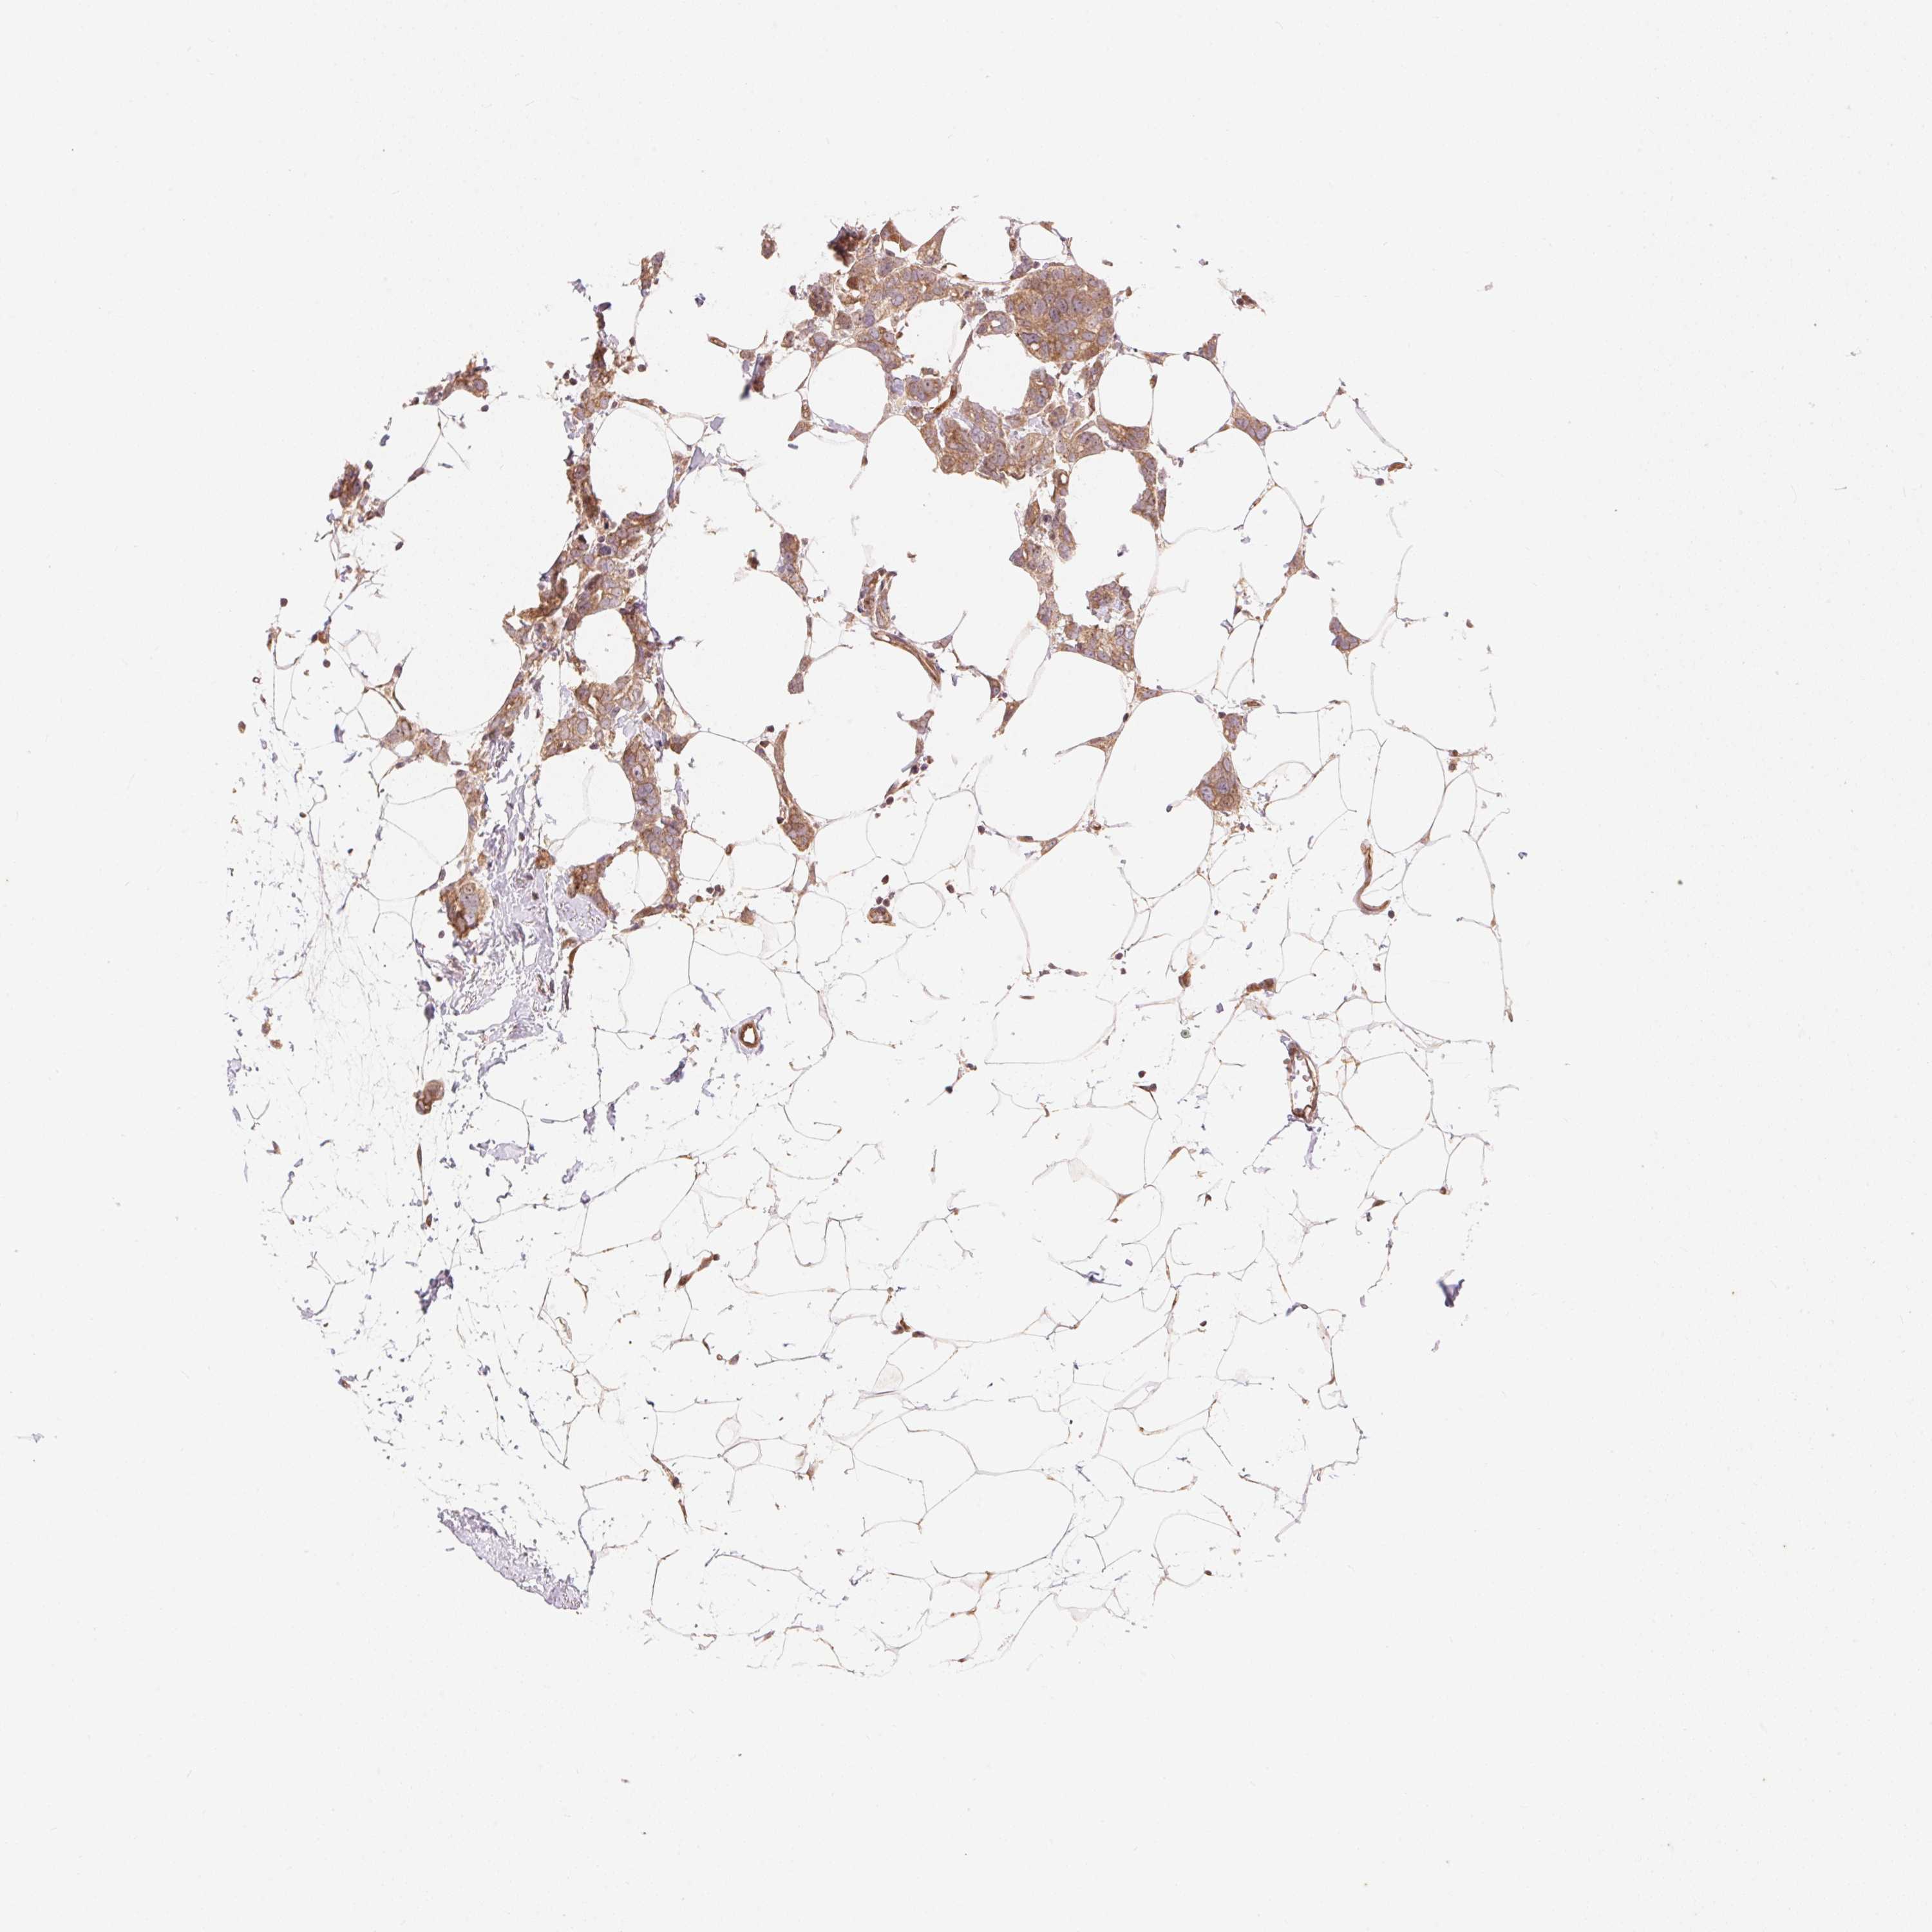

CANCER BREAST CANCER Show tissue menu

BRCA TCGA BRCA VALIDATION PROTEIN EXPRESSION